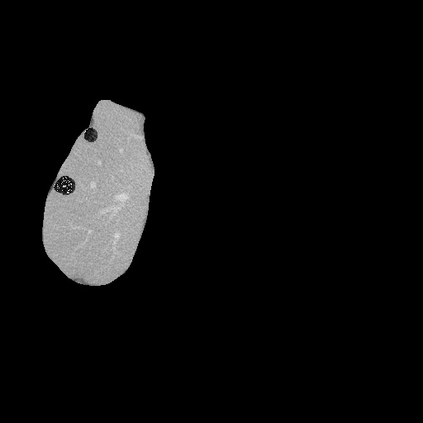

Transformers have made remarkable progress towards modeling long-range dependencies within the medical image analysis domain. However, current transformer-based models suffer from several disadvantages: (1) existing methods fail to capture the important features of the images due to the naive tokenization scheme; (2) the models suffer from information loss because they only consider single-scale feature representations; and (3) the segmentation label maps generated by the models are not accurate enough without considering rich semantic contexts and anatomical textures. In this work, we present CASTformer, a novel type of generative adversarial transformers, for 2D medical image segmentation. First, we take advantage of the pyramid structure to construct multi-scale representations and handle multi-scale variations. We then design a novel class-aware transformer module to better learn the discriminative regions of objects with semantic structures. Lastly, we utilize an adversarial training strategy that boosts segmentation accuracy and correspondingly allows a transformer-based discriminator to capture high-level semantically correlated contents and low-level anatomical features. Our experiments demonstrate that CASTformer dramatically outperforms previous state-of-the-art transformer-based approaches on three benchmarks, obtaining 2.54%-5.88% absolute improvements in Dice over previous models. Further qualitative experiments provide a more detailed picture of the model's inner workings, shed light on the challenges in improved transparency, and demonstrate that transfer learning can greatly improve performance and reduce the size of medical image datasets in training, making CASTformer a strong starting point for downstream medical image analysis tasks.